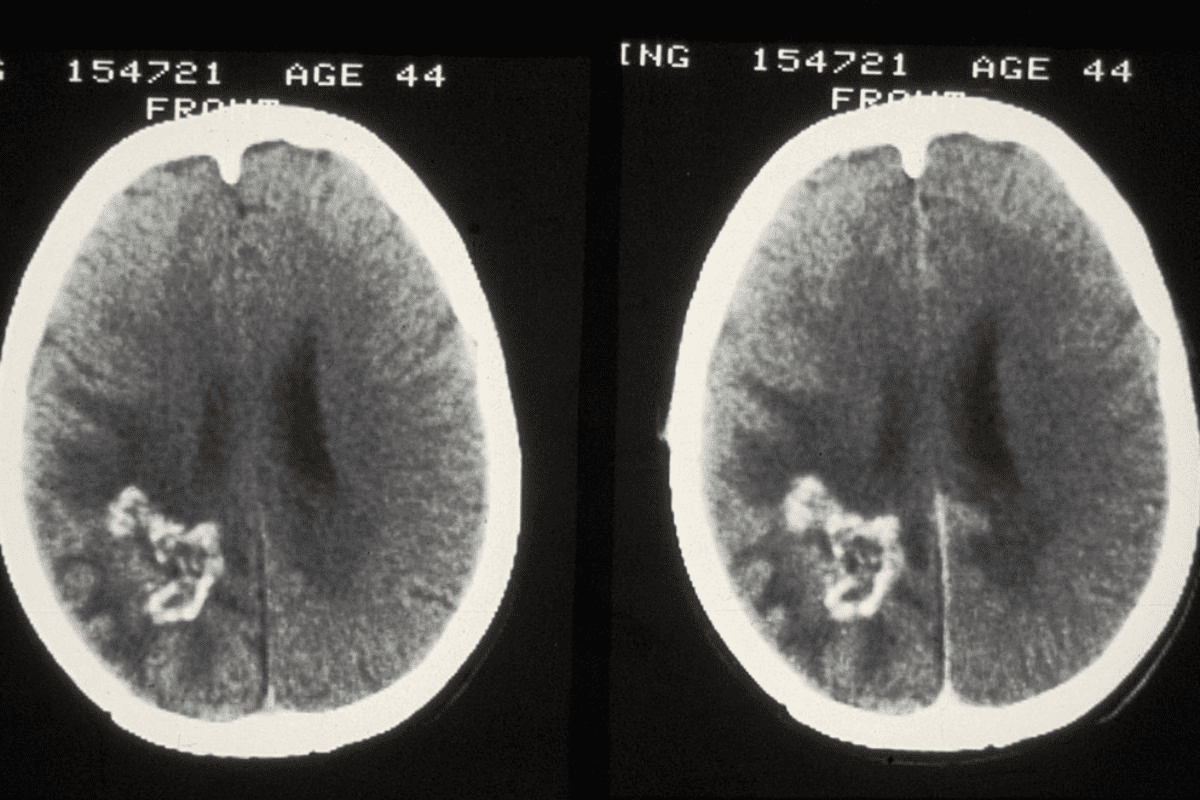

Metastatic Cancer: When Bright White Spots on Bone Scan Indicate Malignancy

Bright white spots on a bone scan often mean metastatic cancer. This is when cancer cells spread to other parts of the body, like bones. It’s a serious issue that needs quick diagnosis and treatment.

Pattern Recognition in Metastatic Disease

Spotting patterns on bone scans is key to diagnosing metastatic disease. Metastatic lesions show up as many random spots of high activity in bones. They can be in bones like the spine, pelvis, ribs, and long bones. The spots’ spread and brightness tell us how far the disease has spread.

A study on theNational Center for Biotechnology Information website shows how important pattern recognition is. It helps doctors diagnose metastatic bone disease accurately.

Common patterns include:

• Multiple focal areas of increased uptake

• Diffuse uptake in a particular bone or region

• A combination of both focal and diffuse uptake patterns